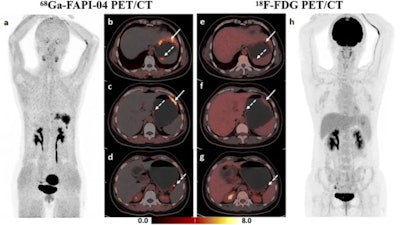

A 66-year-old man was histopathologically diagnosed with gastric antrum adenocarcinoma with perigastric lymph node metastases, and a false-positive uptake of Ga-68 FAPI-04 in the liver was proven to be a fibrotic nodule with calcified schistosome egg deposition without heterotypic findings. (a-c) Ga-68 FAPI-04 PET/CT imaging. Maximal intensity projection (MIP) image of Ga-68 FAPI-04 PET (a), clear recognition of gastric cancer lesion (solid arrow in b) and metastatic lymph node (dotted arrow in b), fibrotic nodule with calcified schistosome egg deposition mimicking liver metastasis (c). (d-f) F-18-FDG-PET/CT imaging. MIP image of F-18 FDG-PET (f), lower F-18 FDG-uptake in gastric cancer lesion (solid arrow in d) and the metastatic lymph node (dotted arrow in d) compared with Ga-68 FAPI, liver lesion showed negative uptake (e).The authors reported that Ga-68 FAPI-04 PET/CT detected more primary lesions (90.3% vs. 77.4%, p = 0.008) and peritoneal metastases (91.7% vs. 41.7%, p = 0.031) and demonstrated higher SUVmax and TBR values (p < 0.001) of primary lesions compared to F-18 FDG PET/CT.